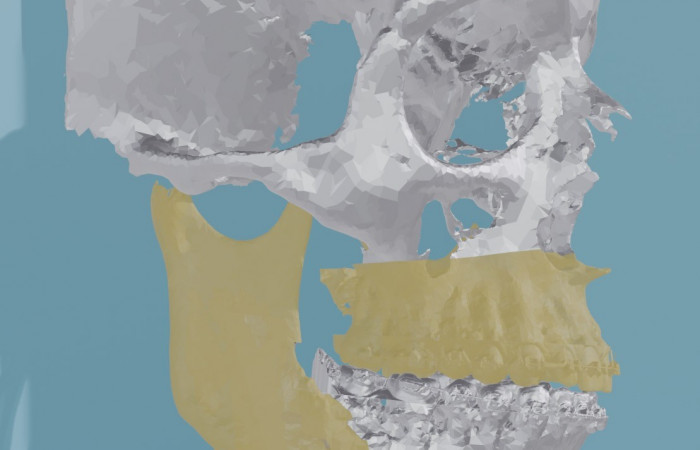

Pracownia Funkcjonalnego i Wirtualnego Medycznego Obrazowania 3D (Pracownia 3D-FM) funkcjonuje w strukturze Zakładu Diagnostyki Obrazowej Szpitala Uniwersyteckiego w Krakowie pod kierownictwem Prof. dr hab. Tadeusza Popieli. Jej celem jest opracowanie i wdrożenie innowacyjnych metod przetwarzania oraz analizy sygnałów i obrazów medycznych, w tym wykorzystanie technologii rzeczywistości wirtualnej oraz metod obrazowania funkcjonalnego. Rozwiązania te wspierają przedoperacyjne planowanie, monitorowanie procedur medycznych oraz wzbogacają proces diagnostyczny o nowe formy wizualizacji danych medycznych.

- Tworzeniem modeli 3D do celów przedoperacyjnego planowania oraz wizualizacji diagnostycznej.

- Obrazowanie Medyczne 3D

- Segmentacja i analiza danych DICOM

- Rekonstrukcja danych medycznych